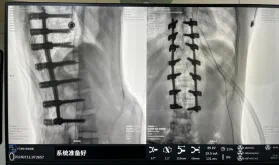

圖為置釘后

據(jù)悉脊柱側(cè)彎手術(shù)治療后可以保持軀干平衡,改善外觀并防止畸形進一步發(fā)展?;颊叩纳钯|(zhì)量得到提高,進而減少脊柱過度畸形可能帶來的疾病的發(fā)生率,外觀上的積極變化往往也能帶來患者心理與精神的積極變化。臨床上會綜合考慮患者的年齡、側(cè)彎程度、進展趨勢、骨質(zhì)條件、鄰近節(jié)段情況、手術(shù)節(jié)段等因素,合理采用個性化的手術(shù)方式進行治療。然而,由于脊柱神經(jīng)血管密布,手術(shù)操作相對復(fù)雜,手術(shù)難度高、風(fēng)險大,傳統(tǒng)脊柱側(cè)彎的手術(shù)方式往往有較高的神經(jīng)或脊髓損傷風(fēng)險。故此次科室決定開展機器人輔助導(dǎo)航下脊柱側(cè)彎矯形、植骨融合內(nèi)固定手術(shù)。術(shù)前,醫(yī)生團隊在機器人多維度圖像融合智能手術(shù)規(guī)劃功能的輔助下,預(yù)先規(guī)劃了理想的置釘路徑。術(shù)中,天璣骨科手術(shù)機器人準(zhǔn)確遵循術(shù)前規(guī)劃,根據(jù)配準(zhǔn)結(jié)果,實時定位并準(zhǔn)確執(zhí)行置釘操作,所有導(dǎo)針均用電鉆置入,一次性成功,協(xié)助醫(yī)生順利完成手術(shù)。最終,在麻醉科、手術(shù)室密切配合下,歷時3小時成功完成側(cè)彎矯形術(shù),出血量僅500ml。術(shù)后,患者恢復(fù)良好,大小便及下肢神經(jīng)運動感覺正常。